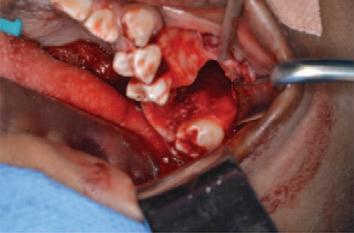

Journal of the Irish dental association by Th!nk Media - Issuu